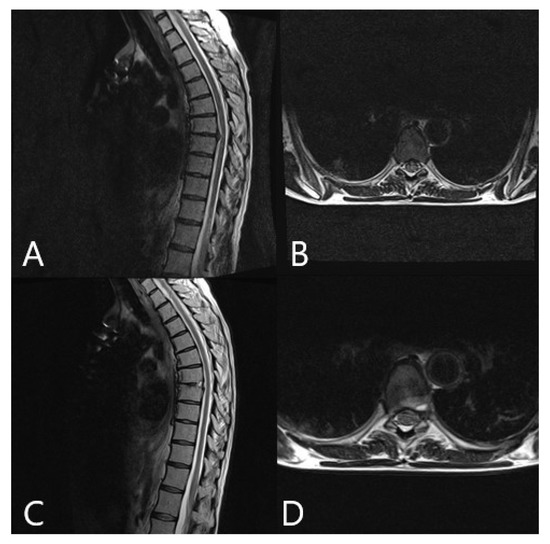

3.4. Augmented Reality

3.5. Clinical Application of iCT and AR